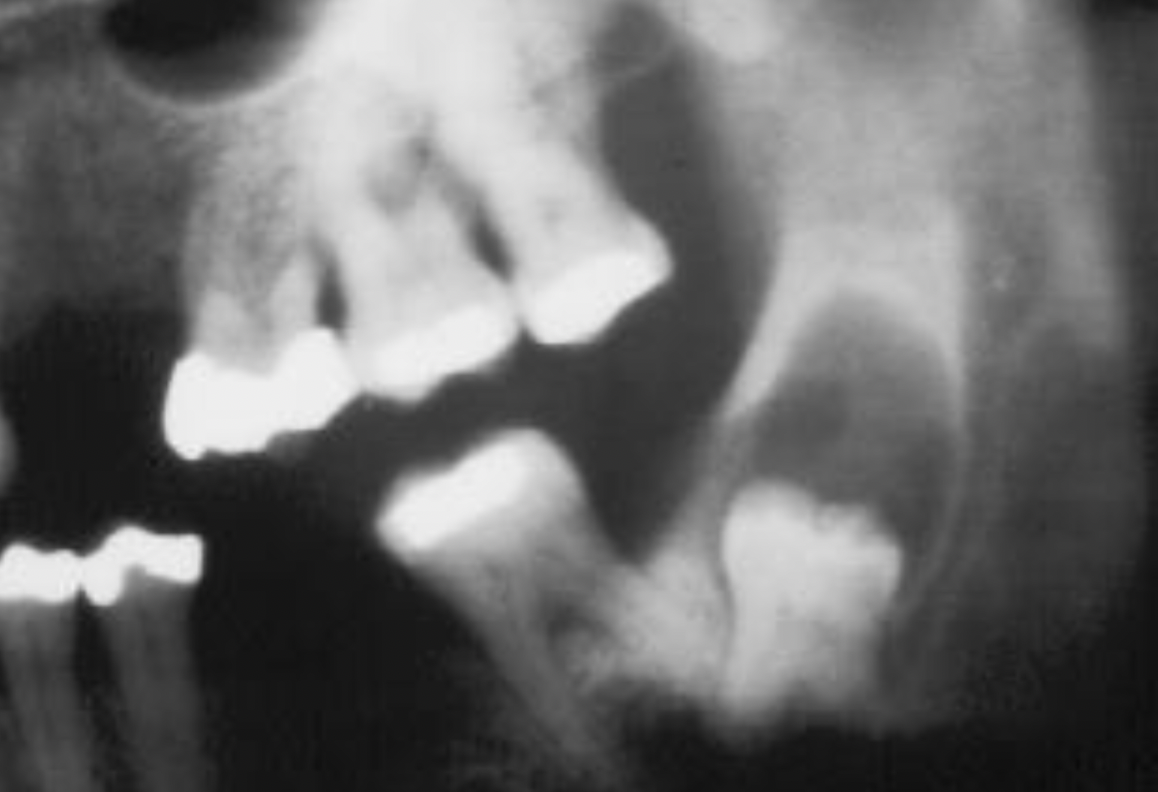

9

A

dentigerous cyst